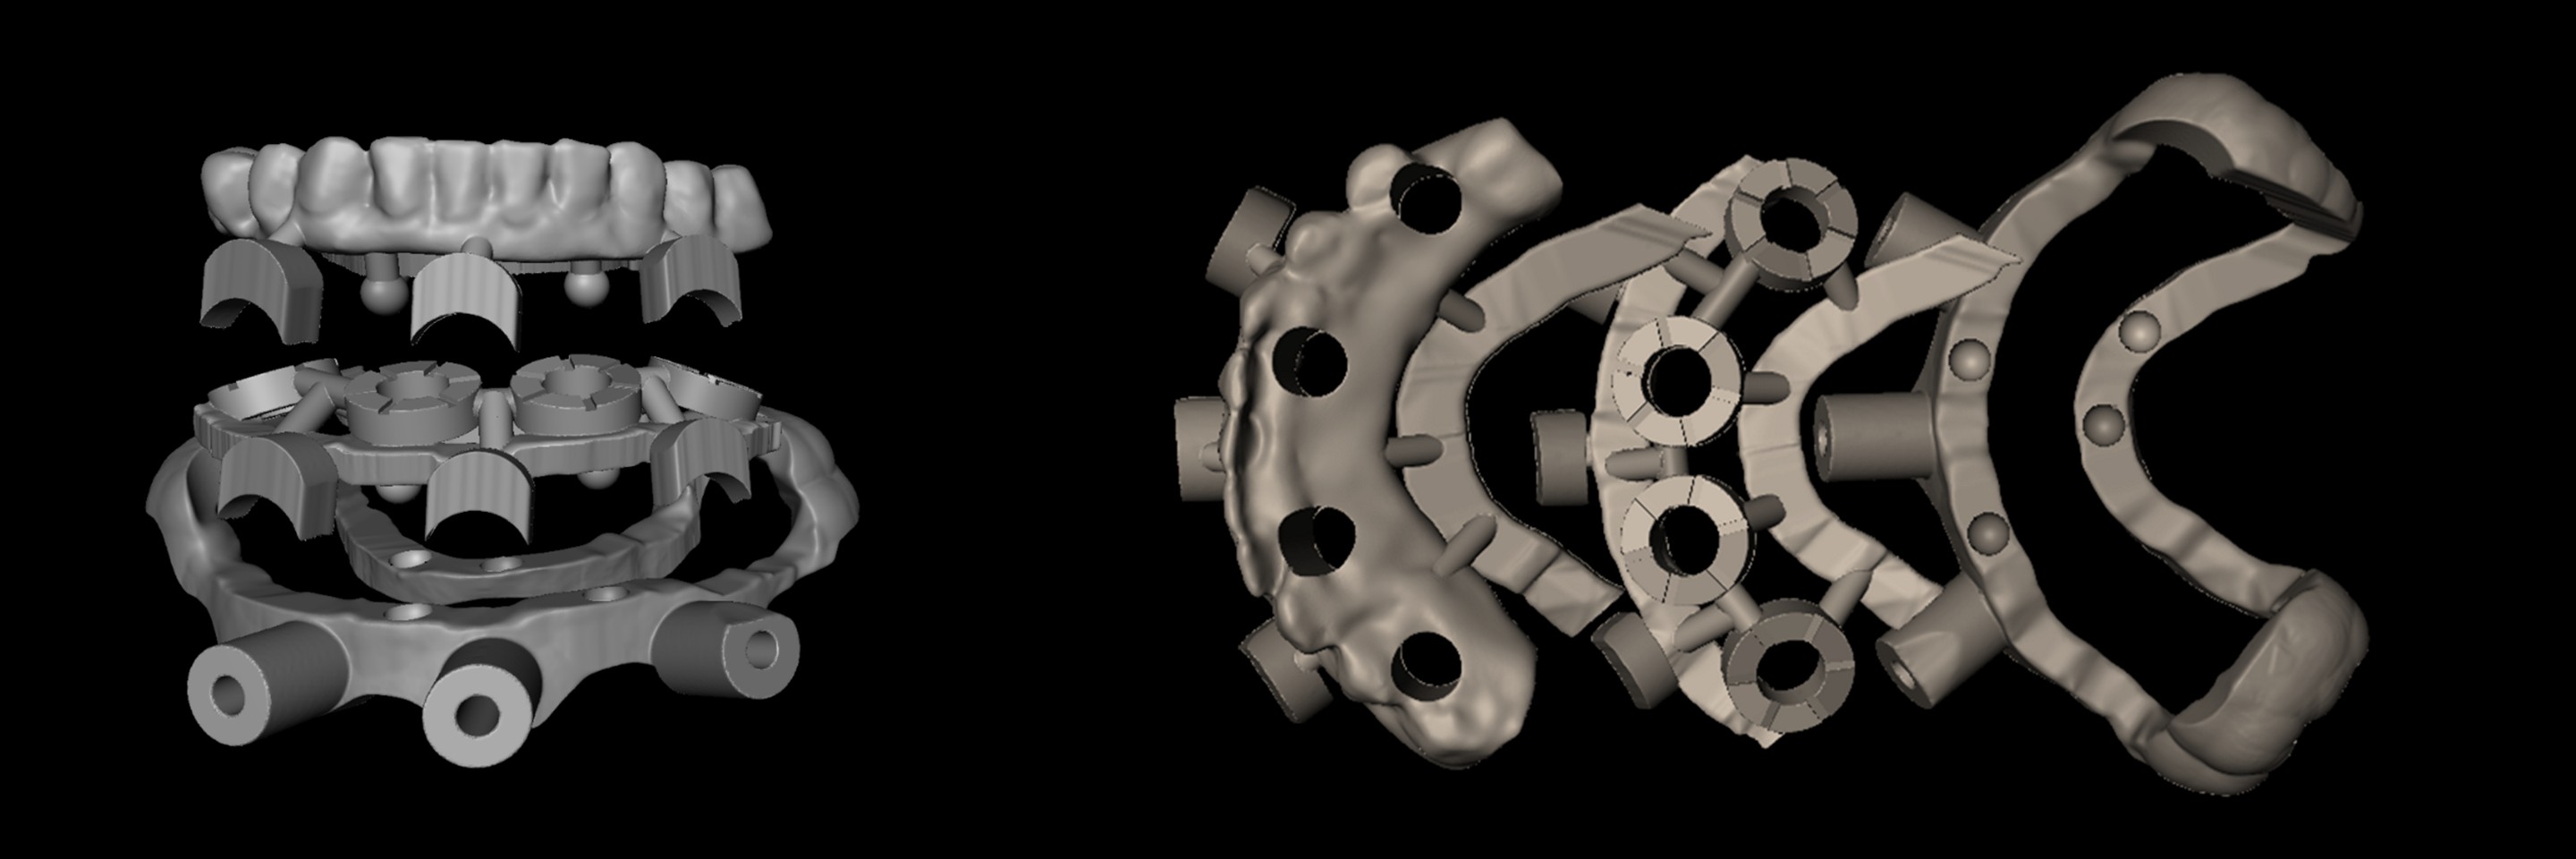

• Bone reduction and Drill guide design hands-on

• Digital surgical guide design and fabrication

• Bone reduction and Drill guide design hands-on

• Digital surgical guide design and fabrication

• Digital-driven treatment protocols with CAD program

• Mastery of CAD program for digital files

• Digital Denture for All-on-X

Director’s Clinical Cases

Director’s Clinical Cases